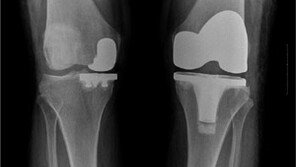

삶의 질이 높아지고, 고령화 사회로 접어들면서 퇴행성 질환에 대한 관심이 높아지고 있다. 단순히 오래 사는 것